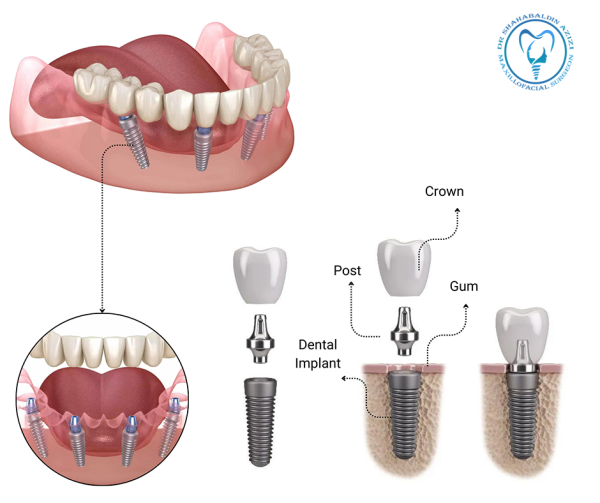

راههای بهبودی سریعتر پس از جراحی ایمپلنت کلید موفقیت در ایمپلنت دندان، مراقبت صحیح بعد از جراحی است. در این مطلب، راههای بهبودی سریعتر پس از جراحی ایمپلنت را بررسی میکنیم. چرا بهبودی پس از جراحی ایمپلنت اهمیت دارد؟ جراحی ایمپلنت یک روش رایج و مؤثر برای جایگزینی دندانهای از دست رفته است. اما پس…